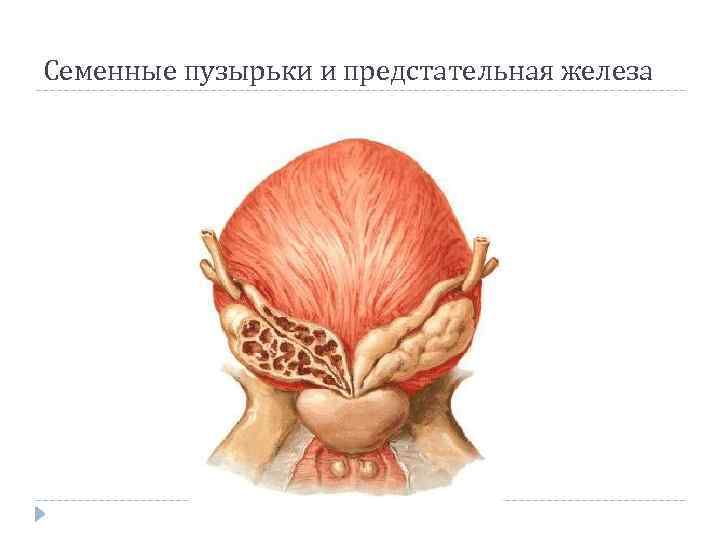

Семенные пузырьки и предстательная железа

Семенные пузырьки и предстательная железа